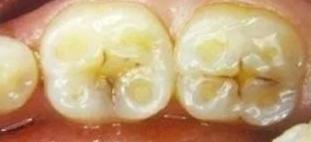

一、牙齿的外源性着色。

*进入口腔的外来色素或口腔中细菌产生的色素沉积在牙面称为牙齿外源性着色。

通俗的说,外源性着色就是因为口腔卫生不良,抽烟熏得,长期喝茶、喝咖啡、喝中药、嚼槟榔等行为导致的牙齿表面,特别是舌面出现的刷不掉的褐色或黑褐色色素沉着。

注:长期用氯己啶(洗必泰)或高锰酸钾溶液漱口或用药物牙膏,如洗必泰牙膏可在牙面形成浅褐或深褐色着色;牙齿局部氨硝酸银浸镀治疗后,相应部位也会变成黑色。